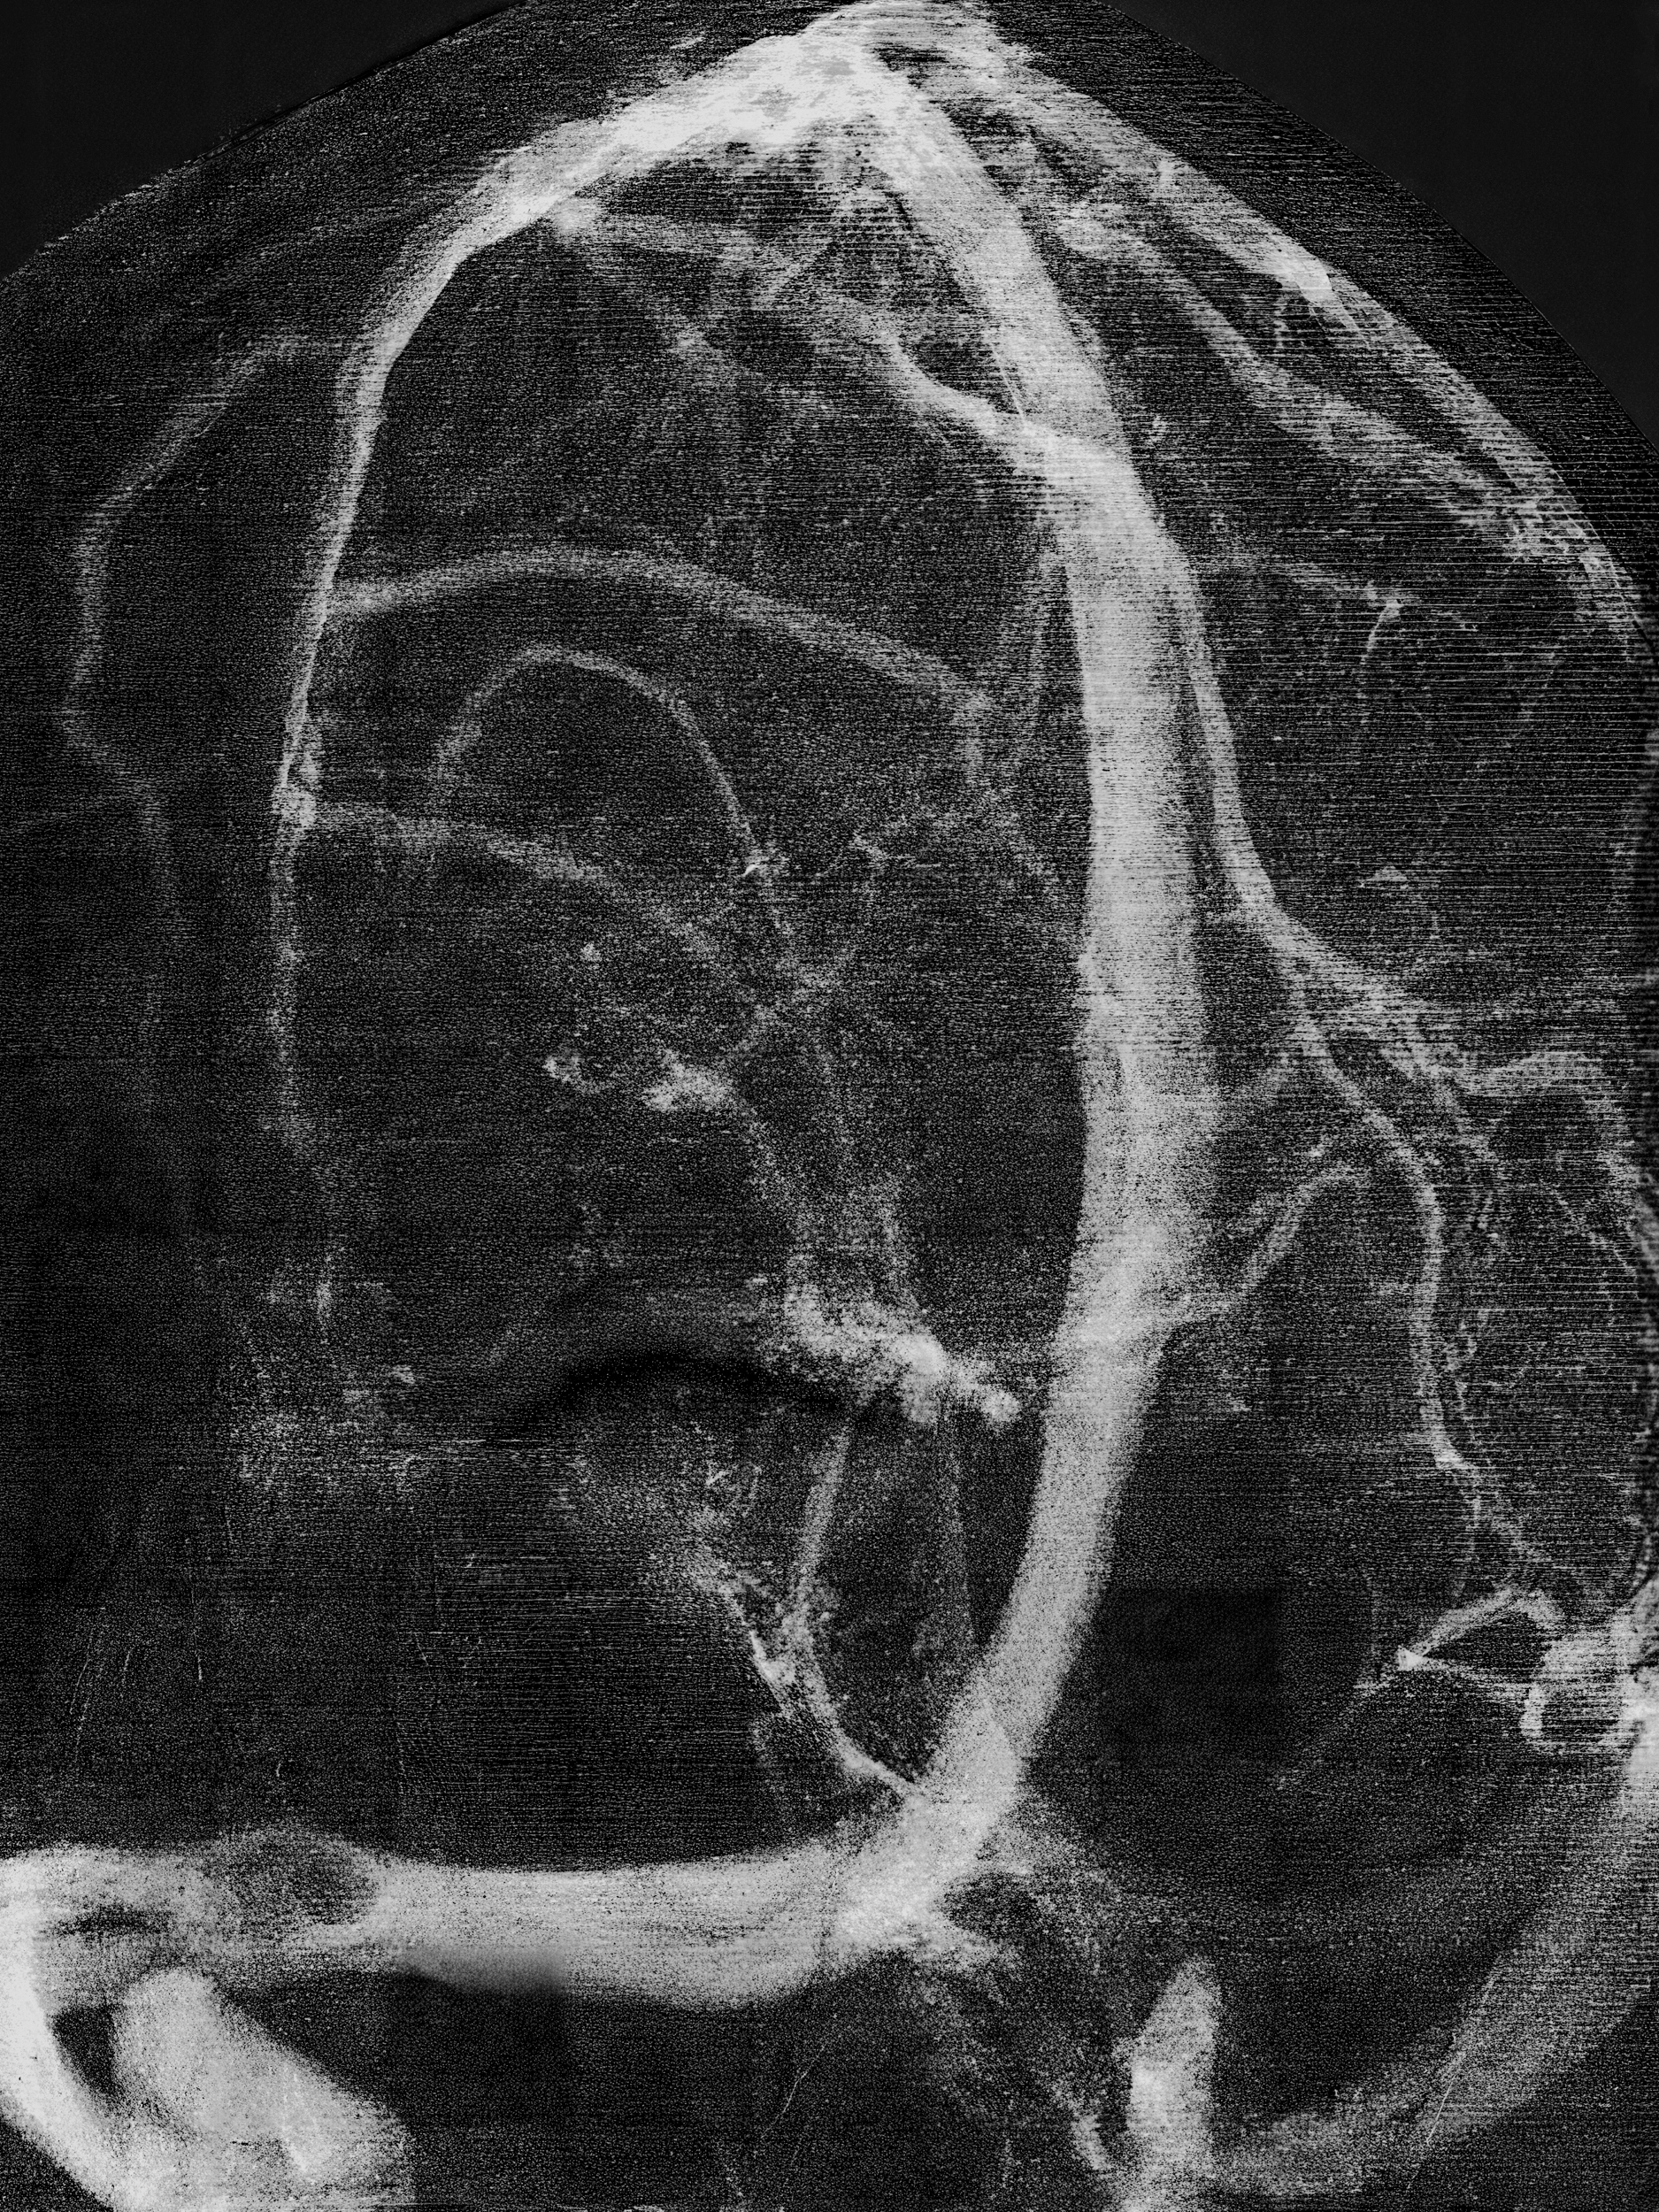

Convolutions

(2023 - ongoing)